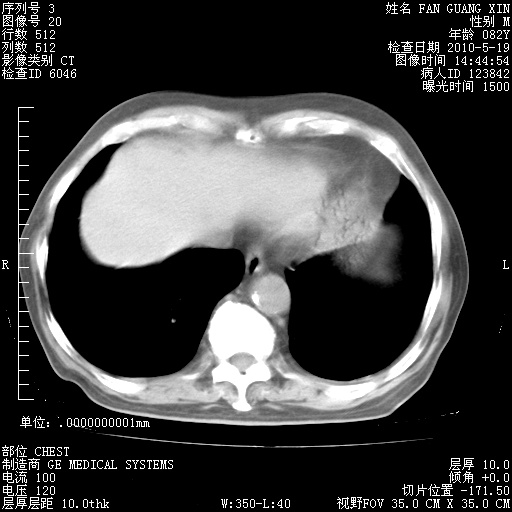

再治疗10天后的肺部CT 纵膈窗

阅读此次胸部CT,肺间质渗出性改变较入院时有吸收。目前从体温、白细胞、中性分叶明显增高,肯定存在细菌感染(发生医院感染哦,若无消化道及泌尿系统等感染的依据,肺部感染可能大)。若你院头孢哌酮舒巴坦钠耐药率较高,同意你的方案,若48小时体温仍高,可考虑使用碳青霉稀类抗菌药物,同时可予超声雾化、注意滴数时加大液体量。白蛋白33.30g/L较低哦,需加强营养等支持治疗。

从白细胞总数和中性比例看好像合并感染。肺部纹理好像比上次多,支气管炎?其他感染?